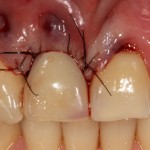

Все началось с воспаления, свищевого хода и удаления зуба:

Затем, мы готовим лунку и проверяем позиционирование импланта:

После чего аугментируем лунку. Для упаковки Bio-Oss Collagen очень удобно использовать аналоги имплантов:

Устанавливаем имплантат XiVE (Dentsply Implants):

Сразу на имплантат — временная коронка:

которая через три месяца, к моменту интеграции импланта, выглядит совсем иначе:

Ну и… к моменту установки постоянной коронки, у нас сохранился естественный контур прилегающей десны.